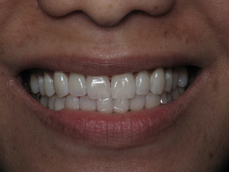

Smile Gallery

Orthodontic Treatment X-ray - Before

After Series of Teeth Extractions, Upper Left Canine Unerupted.

Ready to Start Ortho Treatment

Orthodontic Treatment X-ray - After